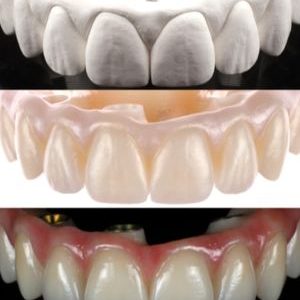

From A to Z Master Hands-On Course for No crestal bone loss